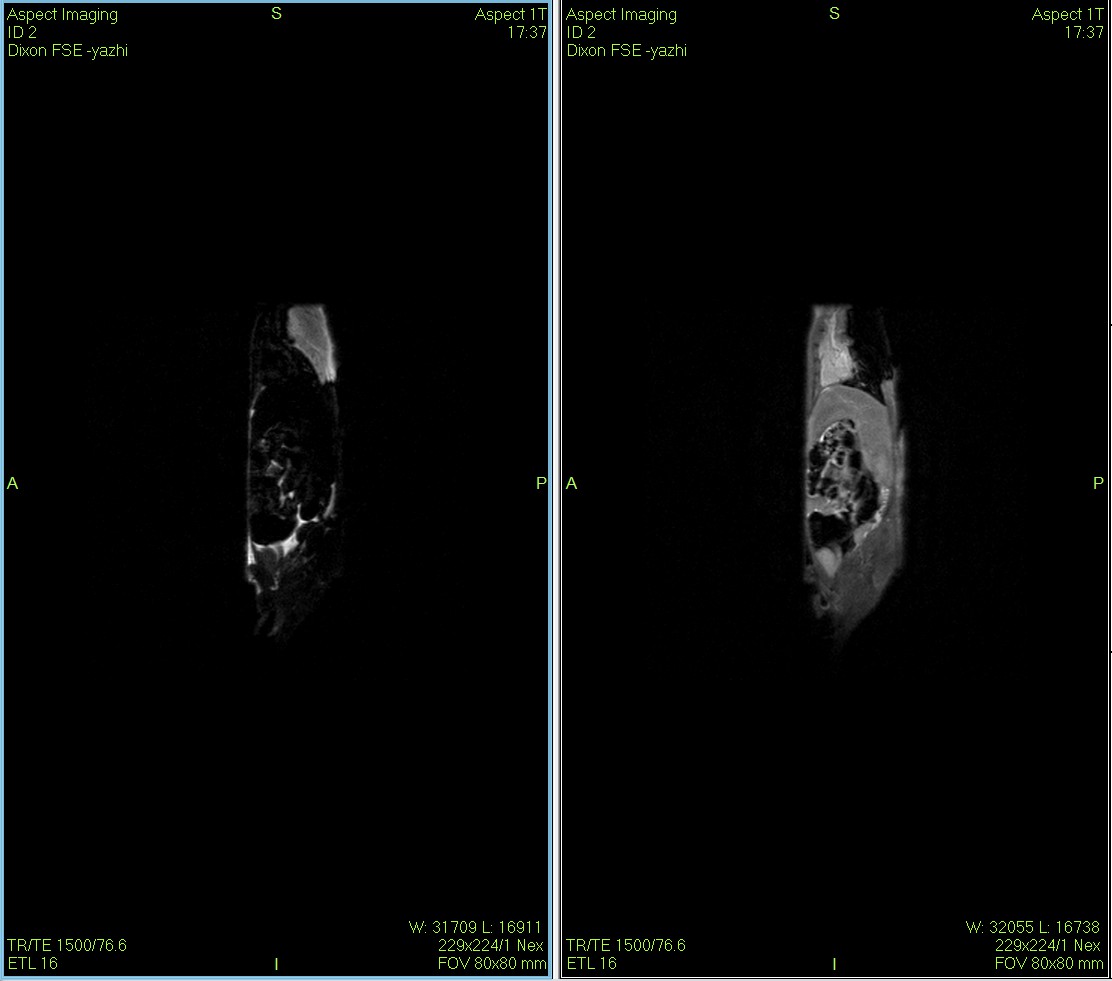

Dixon脂肪抑制技术是由Dixon 提出,其基本原理是利用水、脂肪的化学位移差异,使用不同的回波时问,分别采集水和脂肪质子的in Phase 和 opposed -phase两种回波信号。

小鼠皮下肿瘤MRI造影成像效果与造影剂代谢过程研究。

使用仪器: 小动物核磁共振成像仪NM20-060H-I 其他相关应用: 核磁共振造影剂弛豫率分析造影剂分析案例 核磁共振成像与分析技术在生命科学领域应用解决方案